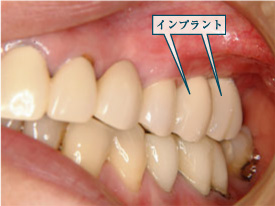

右下顎にインプラントを入れました。

入れ歯の必要がなくなりました。8年経過しています。

人生が変わるほどよく咬めるようになりました。

8年間全く異常を認めません。